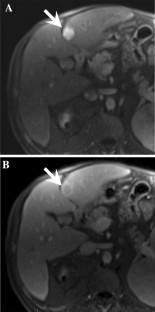

Fig. 4